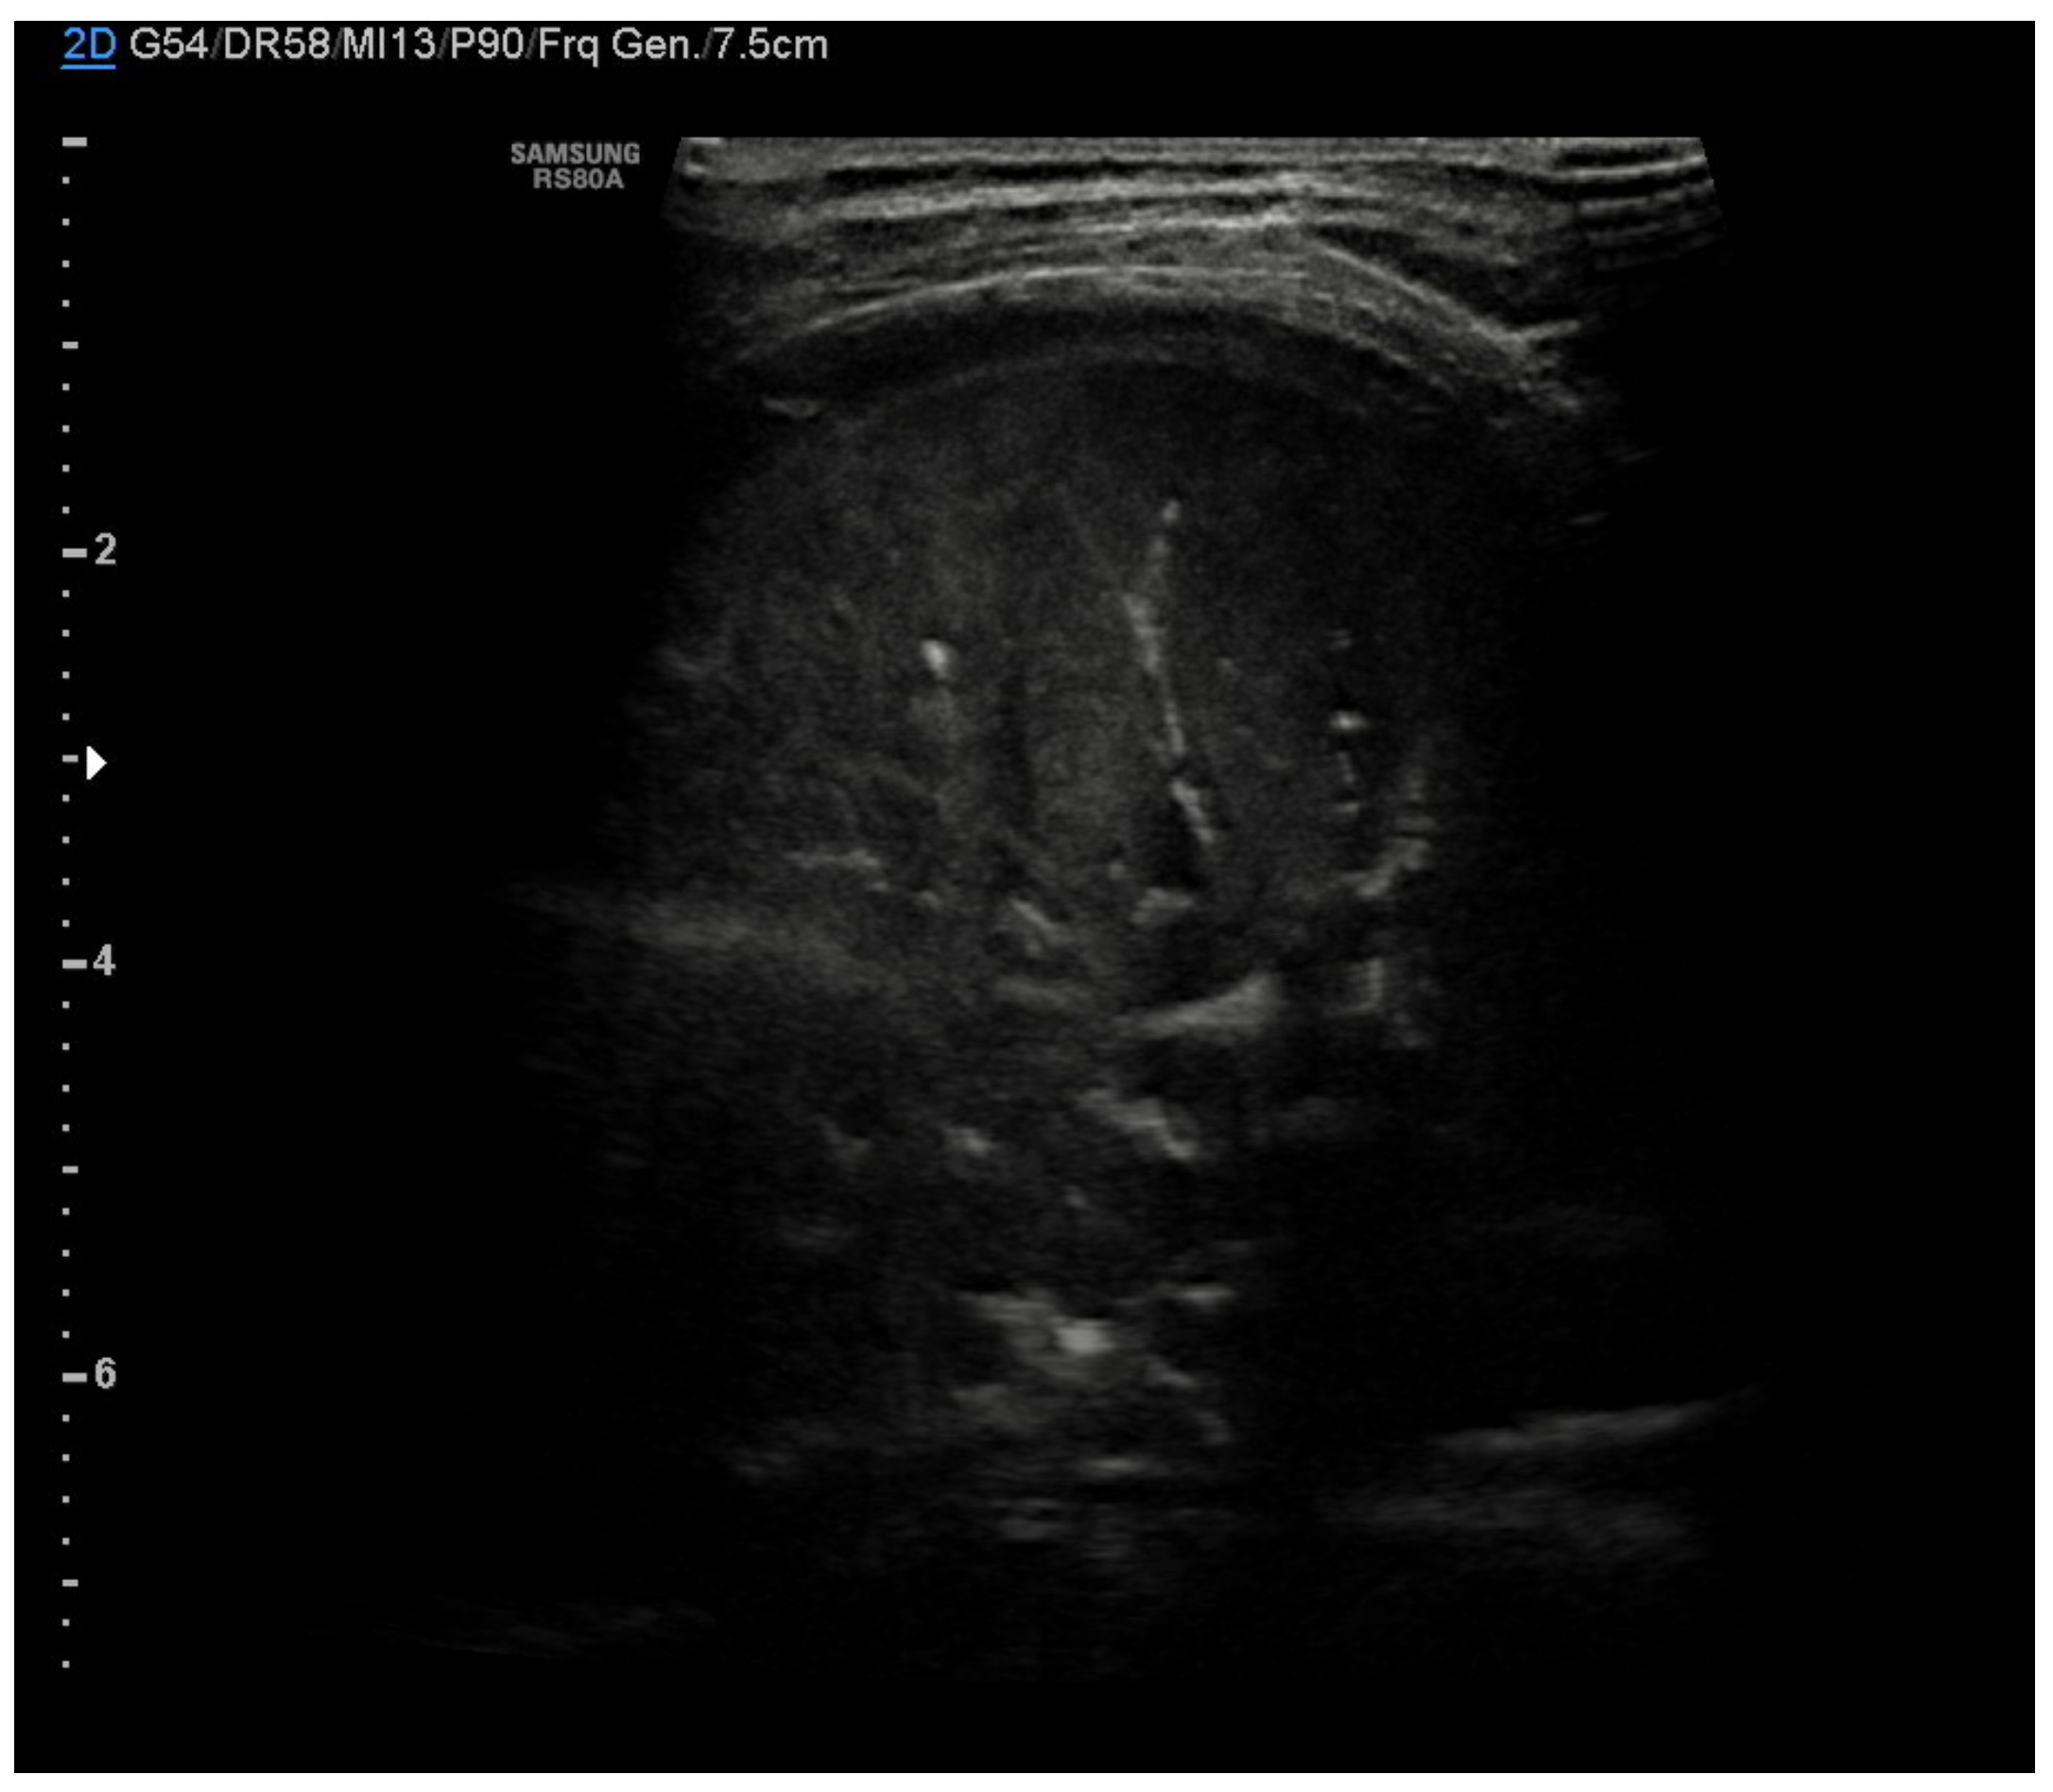

In community-acquired pneumonia (CAP), the main ultrasound findings are consolidations that appear as hypoechoic areas with evidence of an air bronchogram within and an ecostructural “liver pattern,” with clear margins (indicating a lobar consolidation) or surrounded by confluent B-lines (Figure 7) [6].

The liver-like ultrasound appearance, which defines the hepatization of the lung, is consequent to the filling of the alveoli with an inflammatory and purulent material that determines a solid and isoechogenic appearance of the lung. Frequently within the consolidations, it is possible to observe a fine hyperechogenic arborescent pattern that defines the air bronchogram due to the presence of air remaining inside the small bronchioles. The air bronchogram typical of pneumonic consolidations is defined as dynamic due to the possibility of observing the air move back and forth with the breaths, a testament to their patency. This ultrasound sign differs from the static air bronchogram, in which air movement is not observable, typical of atelectasis [38].

Figure 7. Pneumonia. Hypoechoic areas with a liver pattern inside configuring a consolidation. Air bronchogram is visible.